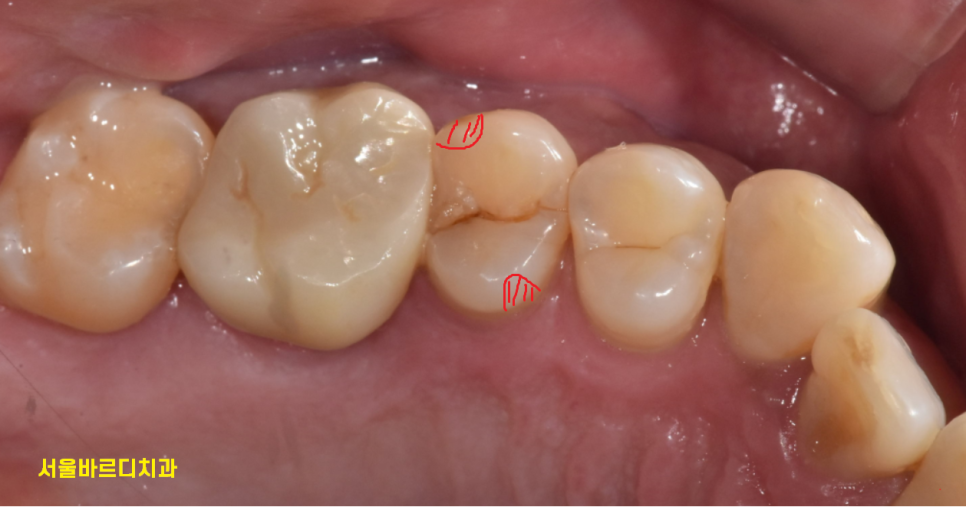

치료는 부위에 따라 달라지는데요.

231102

이렇게 귀퉁이가 약간 깨졌으면

레진

한쪽 귀퉁이가 다 깨졌다.

깨진 부위가 크면 크라운 치료로

치아를 살려볼 수 있습니다.

하지만 오늘처럼 치아가 수직으로

도끼로 나무를 내려찍은듯한 형태인 경우

살리기가 힘듭니다.